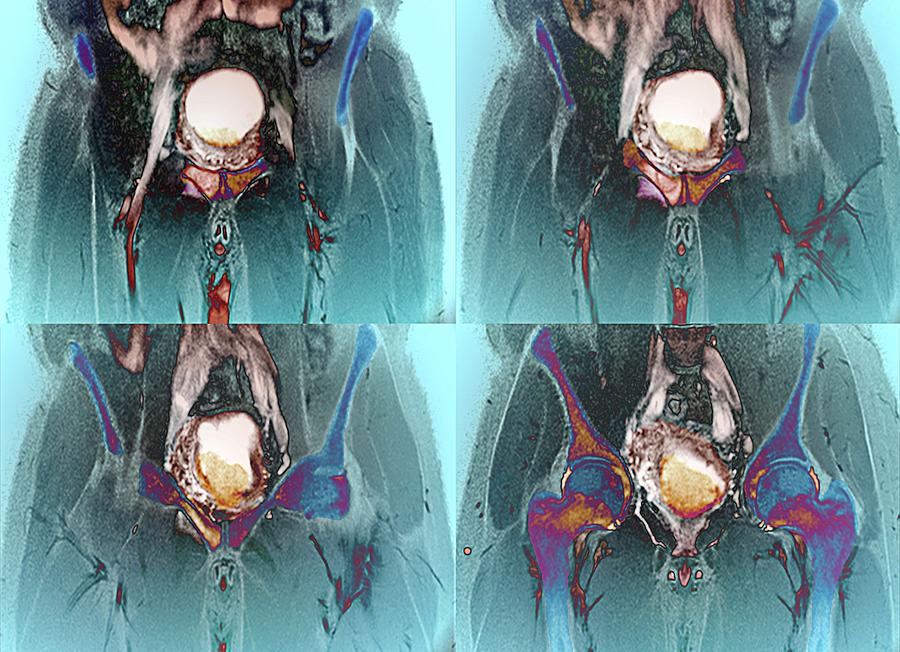

Metastatik mesane kanserinin tanısı, genellikle bir dizi görüntüleme testi, biyopsi ve kan testleri ile konur. İlk olarak, idrar testi ve sistoskopi gibi yöntemlerle mesanede bir kitle veya anormal hücreler tespit edilir. Tanının kesinleşmesi için biyopsi alınarak kanser hücreleri incelenir. Ayrıca, kanserin vücuda yayılmasını değerlendirmek için bilgisayarlı tomografi (BT), manyetik rezonans görüntüleme (MRG) veya pozitron emisyon tomografisi (PET) gibi ileri görüntüleme yöntemleri kullanılabilir.